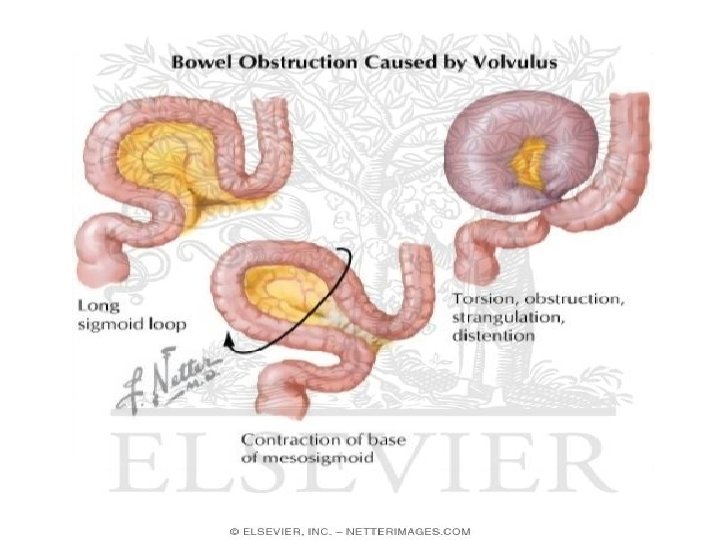

• Okluzioni mekanik vjen nga patologji qe kane origjinen ne lumenin e zorres, ne murin e saj dhe strukturat indore fqinje. • Okluzioni intestinal nga strangulacioni shoqerohet edhe me bllokimi te menjehershem te eneve te gjakut dhe me nderprerjen e qarkullimit te gjakut.

• Okluzioni intestinal pasohet nga zgjerimi i segmentit te zorres (mbi pengese), tensionim dhe hollim te murit te saj. • Nderlikohet dhe perkeqsohet edhe qarkullimi I gjakut (venoz, kapilarve arterial) e deri ne paraliza te zorres me crregullime te permeabilitetit te murit te zorreve --crregullim te perthithjes se lengjeve dhe kriprave---duke krijuar substanca te panevojshme dhe te demshme per organizmin

• Te gjitha keto ndryshime krijojne nje gjendje te rende me pasoja te pergjithshme qe shprehen me: - crregullime te thella hidro-elektrolitike (Hipo. Na, K, Cl) - Hemokoncentrim relativ - Gjendje septike nga peritoniti difuz i shkaktuar nga bakteriet gram (-) qe vijne nga rritja e permeabilitetit te zorres dhe perforacionit te saj.

Volvulus i kolonit sigmoid